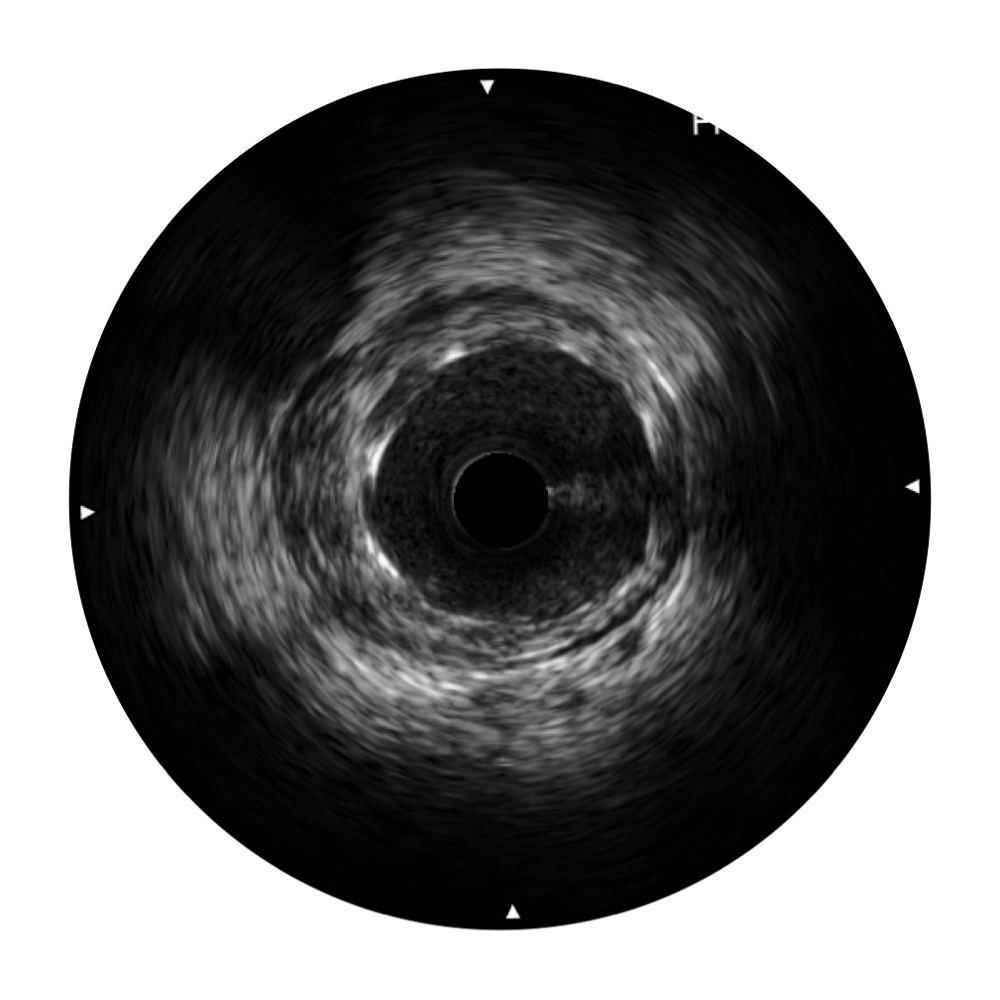

開立寬頻IVUS圖像

傳統(tǒng)IVUS圖像

對比傳統(tǒng)IVUS導(dǎo)管成像,開立寬頻IVUS圖像的近場支架梁顯影更細(xì)膩,遠(yuǎn)場中膜外血管仍清晰可辨,兼顧遠(yuǎn)中近,兼顧分辨力與穿透深度